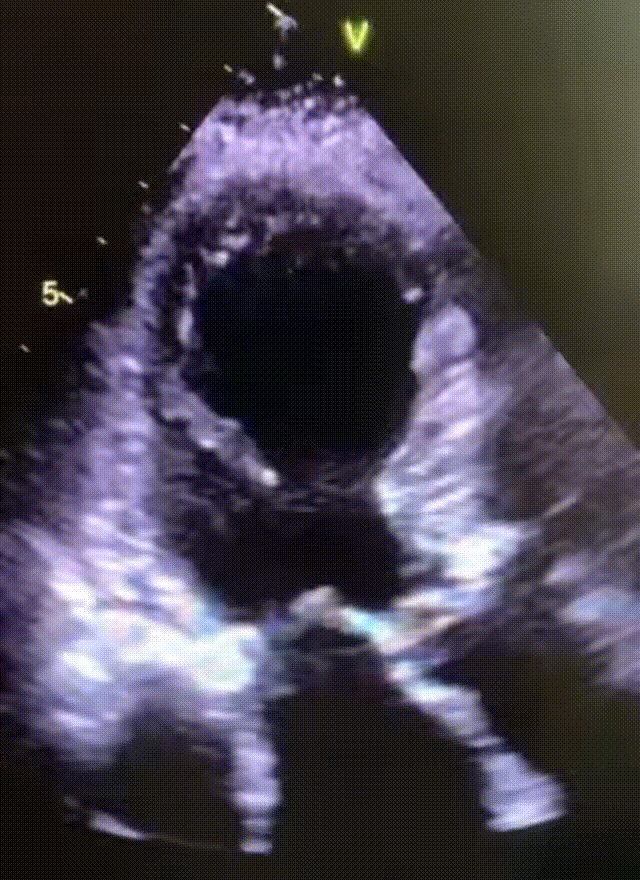

感谢我们医院心超室的叶医生每次都能打出漂亮的心尖球囊样改变的超声动图(即传说中北海道的“章鱼壶”样),让每例应激性心肌病都有一个完美的闭环。

第1例:2025.9.26骨科会诊的病例。83岁女性,腰椎术后+紧张焦虑诱发。再经典不过的应激性心肌病的心肌图(广泛T波倒置,胸导V3-V5的T波倒置最深,胸导II导的T波倒置最深,经典的指向心尖部的完美向量,秒杀),心超下的动图也是相当的经典的心尖球囊样改变(即传说中北海道的“章鱼壶”样)。其实这个病人4年前已经在我们科室发作过一次应激性心肌病,当时已经做了左室造影证实。这次是复发,自从广东省人民进修回来诊断的数十例应激性心肌病当中,第一次遇到复发的。